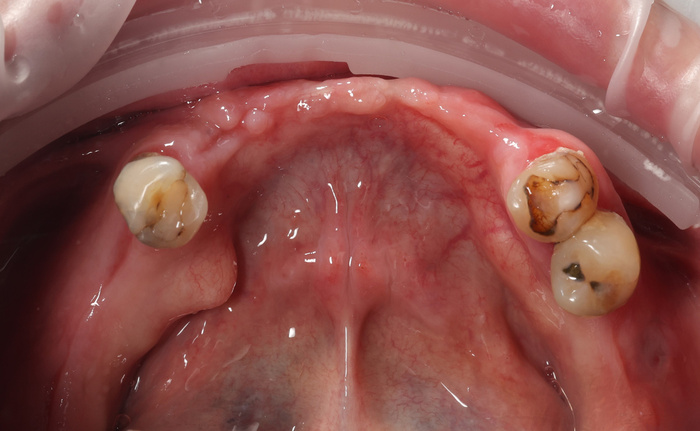

Делаем фото до:

И во рту:

Да и смысл добавлять скан - всё видно и понятно. На нижней челюсти 4 зуба, которые никуда не годятся.

Справа - одинокий воин.

Слева - компания друзей навынос.